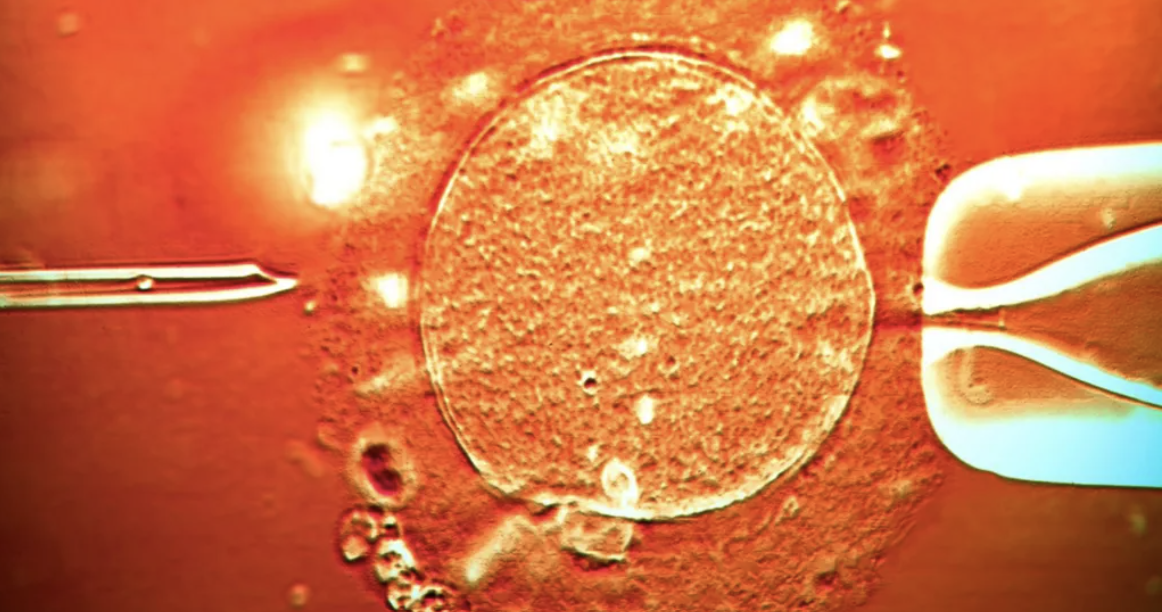

The sperm came from an anonymous man who was paid to donate as a student, starting in 2005. His sperm was then used by women for around 17 years.

Most of the donor's body does not contain the dangerous form of TP53, but up to 20% of his sperm do.

However, any children made from affected sperm will have the mutation in every cell of their body.